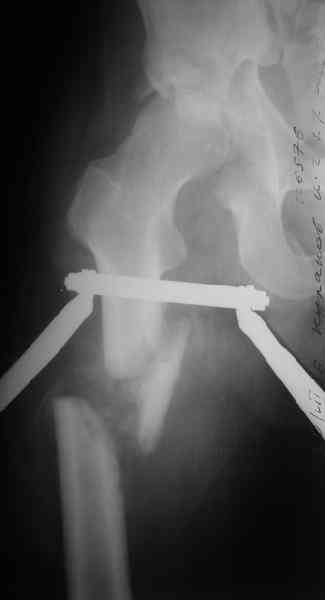

Уважаемы коллеги! Поступил непростой больной 24 лет через 1 месяц после травмы (фото в приложении). Кроме перелома правой вертлужной впадины, перелома и вывиха этого же бедра имеются переломы диафиза правой плечевой кости, диафиза правой локтевой кости, диафизов обеих костей левого предплечья.

Неврологии со стороны нижних конечностей нет. Планируем первым этапом выполнить ЗИМО длинных трубчатых костей. Вопросы: 1. имеет ли смысл в эти сроки идти на остеосинтез вертлужной впадины и вправление вывиха или планировать первичное эндопротезирование? 2. Есть у кого-нибудь ссылки или другая информация по поводу исходов лечения переломов вертлужной впадины, сопровождающихся вывихом головки бедра в разные сроки (буду очень признателен, если поделитесь)?A male 24 y.o, admitted to our unit today 1 month post injury - images attached. Except ipsilateral acetabular fx, femoral shaft fx and hip dislocation also he has shaft fxs of right humerus and ulna, left radius and ulna. No neurological deficits after the hip dislocation. At first we plan closed nailing of all long bones. Questions are regarding the acetabular fx + dislocation. With the 1 month of exposition and obvious callus everywhere does it make sense to attempt ORIF of the acetabulum with hip reduction, or primary THA should be considered? Does anybody have references on outcomes after delayed surgeries for acetabular fx + hip dislocation depending on duration of the delay? С уважением Максим Агалаков, УНИИТО Е-бург.